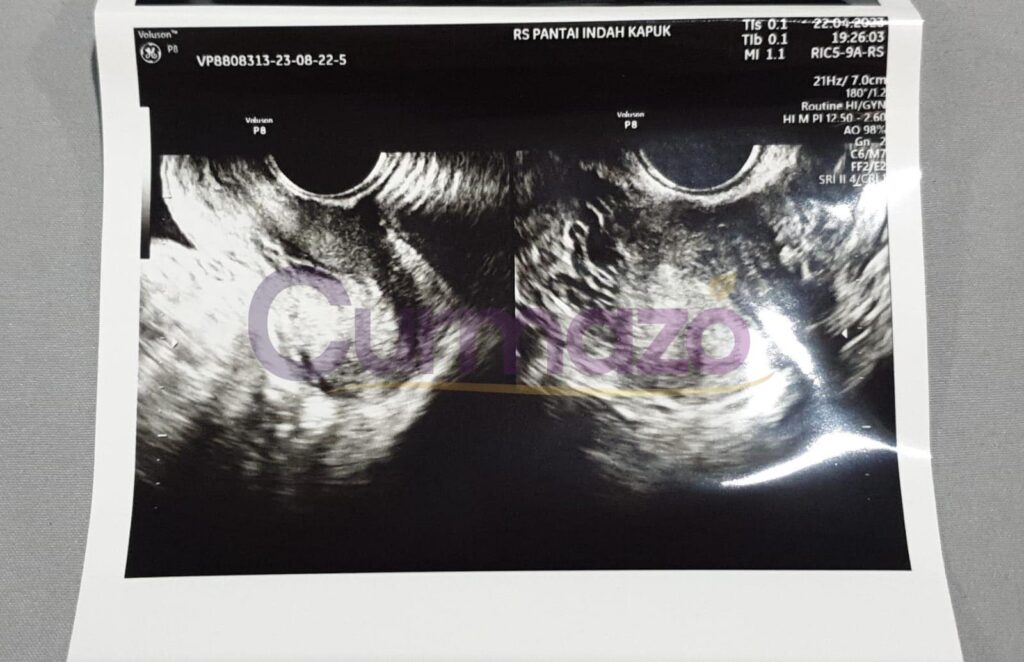

Foto hasil USG before:

Tanggal 5 Oktober 2025 saya USG di dokter yang sama, dokter kaget lihat kista saya sudah tidak ada. Sebelumnya saya juga tidak menyangka kalau hilang total, pikir saya kalo mengecil aja udah alhamdulillah banget tapi justru hilang total. Dokter juga gak nyangka, akhirnya USG lagi sampai 3 kali. Namun, hasilnya tetap sama saja 3 kista sudah tidak ada yang berarti hilang total!

Foto hasil USG after: